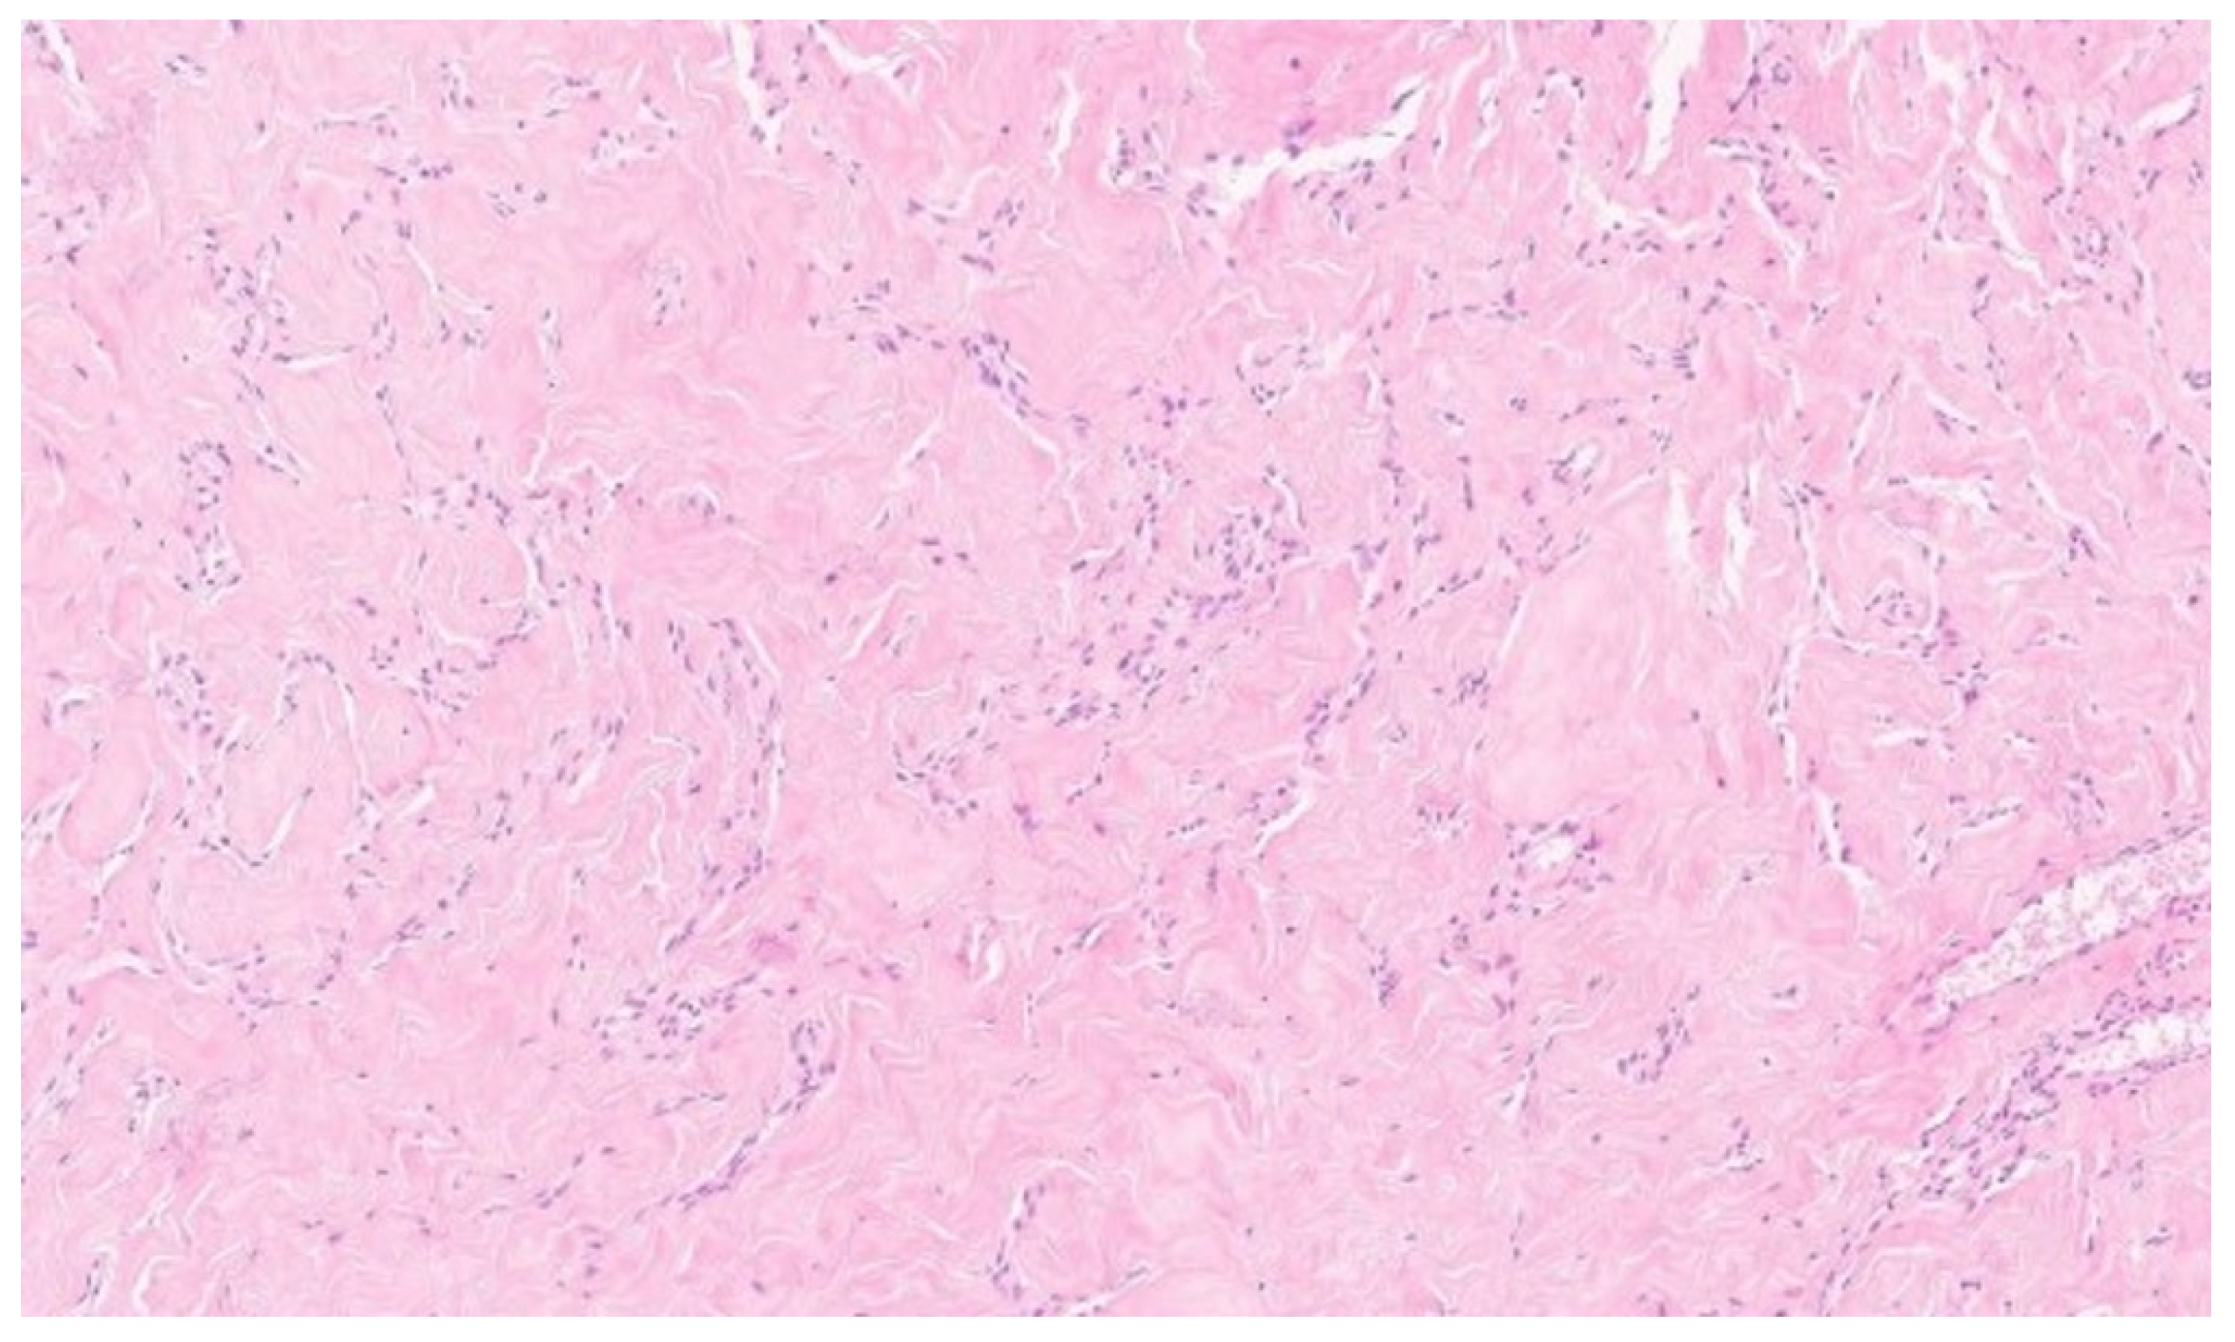

Due to the size of the lesion, diagnostic evaluation was extended to include magnetic resonance imaging (MRI). MRI confirmed the previous findings, showing a well-circumscribed lesion without diffusion restriction. No additional focal pathological changes were detected. No pathological lymph nodes were visualized in either axilla (levels I, II, or III). MRI was classified as BI-RADS category 4 for the left breast and category 1 for the right breast (Figure 1).

Figure 1. Magnetic resonance imaging of the left breast. Axial T1-weighted contrast-enhanced sequence reveals a large, homogeneous tumorous lesion, indicated by white arrows.